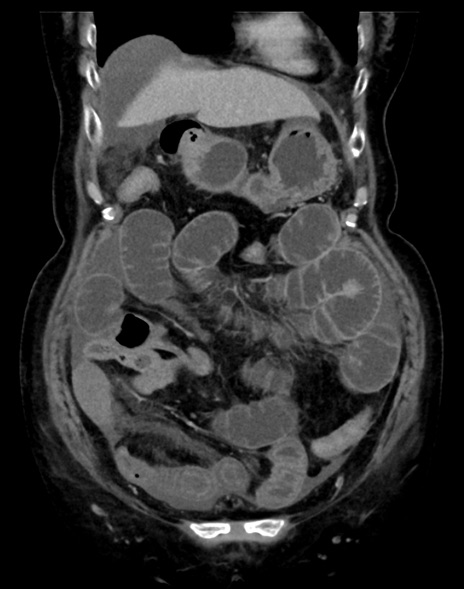

症例13 CT(冠状断像)1日半後